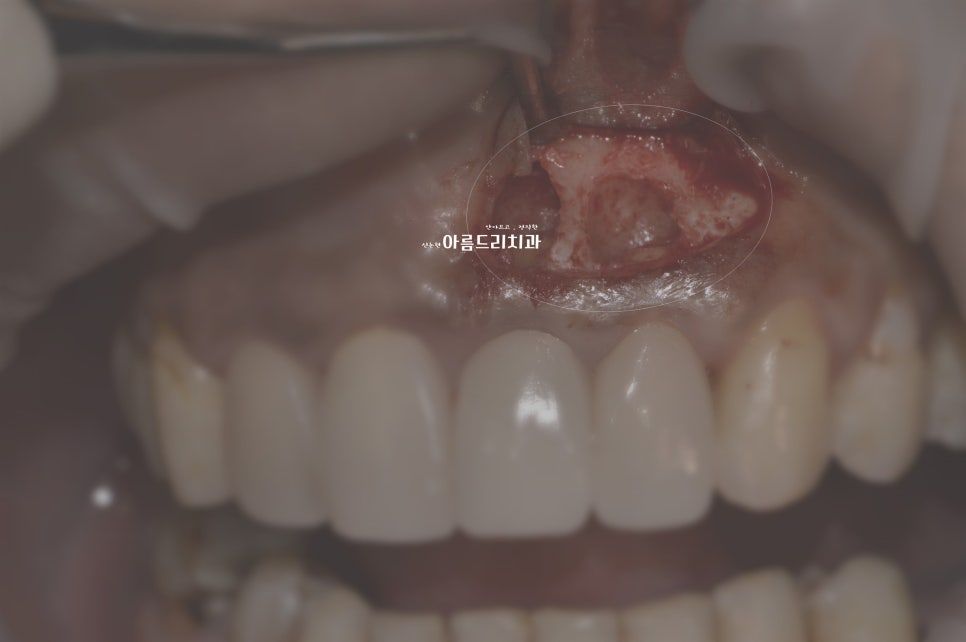

앞니 쪽에 지속적으로 통증이 있어 진단 후 치근단절제술을 시행하기로 하신 케이스로, 뿌리 조직의 염증을 제거 후 부족한 치조골(잇몸뼈)에 뼈이식으로 함께 진행합니다.

치아뿌리염증 _치근단절제술

치근단 절제술 후 뼈이식

*위 시술 사진은 다소 불편한 장면이 포함되어있어 색보정이 되었음을 알려드립니다.

치근단절제술 하긴 전 병변 사진 (붉은색으로 표시)